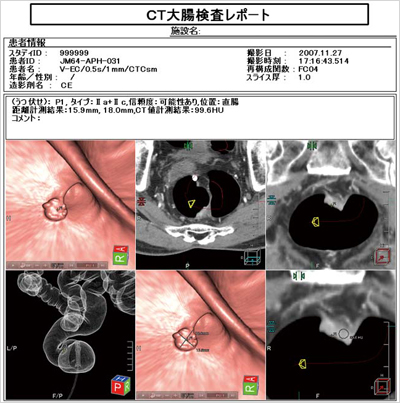

観察の過程で病変の疑われる部分を登録し,病変ごとにコメント入力やキー画像の保存ができる。位置情報を同時に登録するため,再度その部分を観察する際にも移動が容易となる。

保存されたコメント,キー画像は,レポートやDICOM画像として出力することも可能である(図6)。 |

図6 CT大腸検査レポート画面 |